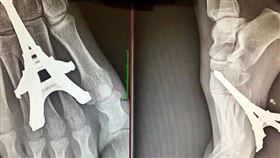

痛!赤腳誤踩鐵塔模型 整根鑽入腳掌

在家盡量穿拖鞋,不然就是要多多留意地上的情況。最近一...